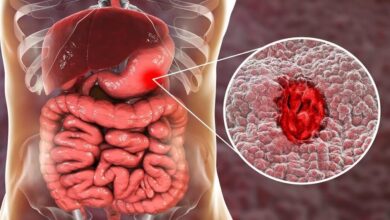

- وتعتبر أمراض الكلية دليل على العلامات المتقدمة لزيادة نسبة الأملاح في جسم الإنسان.